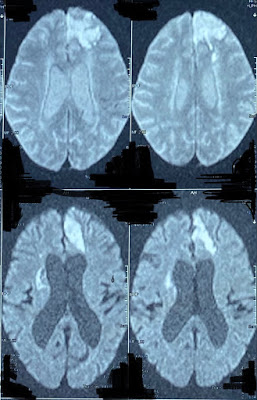

1. Ultrasound

3. MRI